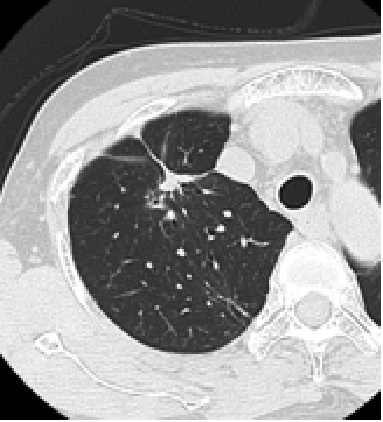

症例1

右原発性肺がんの症例ですが、ラジオ波治療を行うと、約半年後には腫瘍は死滅し瘢痕状となっています。

治療後